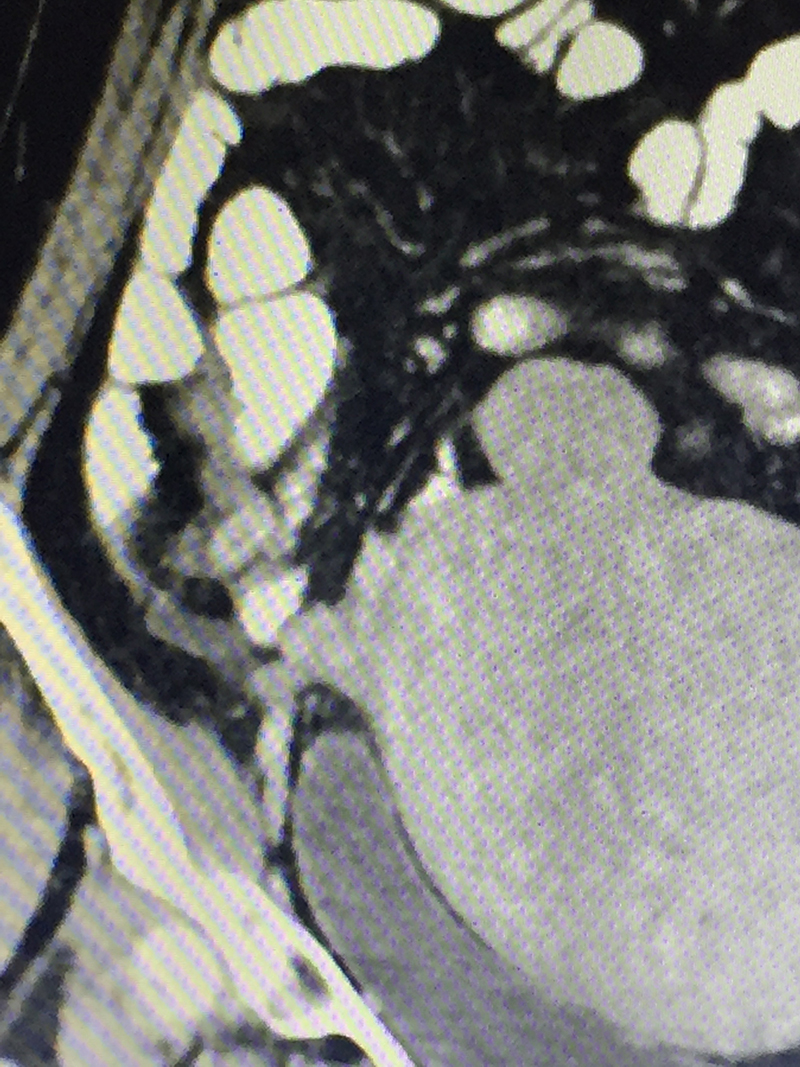

50 year old lady with acute abdominal pain in the right lower abdomen, vomiting and fever was diagnosed with acute appendicitis. Preliminary blood investigations & ultrasonography corroborated the diagnosis. A CT scan of the abdomen and pelvis was done to confirm the diagnosis & look for complications like perforation & abscess. An acute appendicitis with localized perforation & infected fluid collection was observed. She also had a large fibroid in her uterus. As is our policy (most acute appendicitis patients are treated by laparoscopic surgery), patient underwent a laparoscopy. At the time of laparoscopy, a perforated gangrenous appendix was found with a large walled off pus collection in the abdomen. The huge fibroid made the surgery difficult since it kept on coming in the line of surgery. However the appendicectomy was successfully completed laparoscopically and patient was discharged on 4th postoperative day. Due to the existing infection, a hysterectomy for the fibroid was not performed at the same time. It was done later after few months.

When there is a clinical suspicion of acute appendicitis, he / she is subjected to blood (CBC / CRP) investigations and imaging study (Ultrasonography). Severe colitis / enteritis / mesenteric lymphadenitis, ileal perforation, intestinal tuberculosis, inflammatory bowel disease, colonic diverticulitis, pericolic appendagitis, Meckel’s diverticulum etcetera can have present with similar symptoms and signs. Some of these diseases can be managed with medicines alone. Hence a CT scan of abdomen and pelvis with oral and intravenous contrast is advised before any surgery is planned for appendicitis. CT scan not only confirms diagnoses, but also reveals complications like perforation, abscess etcetera or an alternative diagnosis or associated malignancy (as in elderly patients).